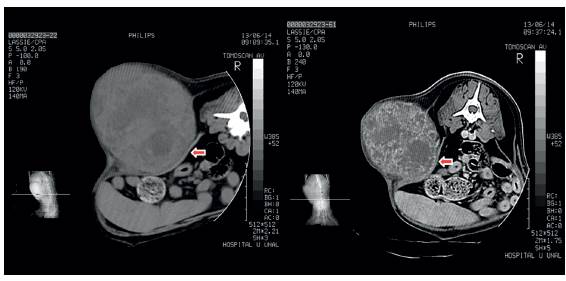

Debido a que los hallazgos radiográficos no fueron concluyentes, se realizó una tomografía computarizada con el fin de delimitar la masa y observar el posible compromiso de los órganos abdominales; en dicha tomografía se observó una estructura de gran tamaño en la pared abdominal izquierda que abarcaba la región abdominal desde el aspecto caudal de la decimosegunda costilla, hasta la altura de la séptima vértebra lumbar, y desde los músculos dorsales epaxiales hasta el borde abdominal ventral; la masa mostraba una forma ovalada con bordes irregulares y densidad de tejido blando (Figura 1). En la porción craneal de la estructura se observó lesión monostótica de la decimotercera costilla izquierda debido a la cual se deformó su recorrido en el tercio medial y distal. No se observó osteólisis; sin embargo, los márgenes corticales mostraron reacción perióstica moderada y desplazamiento periférico de fragmentos óseos y zonas multifocales con densidad ósea que pueden corresponder a focos de mineralización neoplásica. En los cortes transversales se apreció contacto de la masa con el peritoneo y desplazamiento de las vísceras abdominales hacia la derecha del plano medio (Figura 1); sin embargo, la estructura no involucró la cavidad abdominal ni la pared peritoneal.